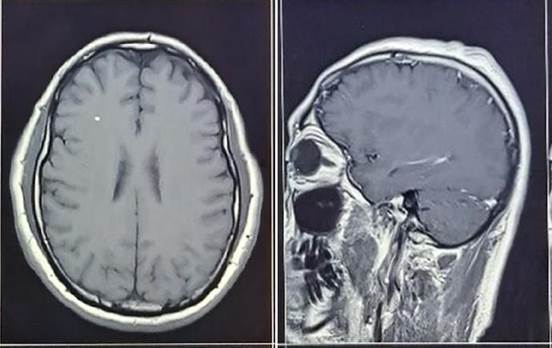

Varón de 47 años, natural y procedente de Lima, con un tiempo de enfermedad de 15 meses, caracterizado por parestesia ascendente y aumento de tonicidad en miembro superior derecho asociado a cefalea de moderada intensidad a predominio frontal e inyección conjuntival en ojo izquierdo. Presentó pérdida de conciencia por lo que fue llevado a la sala de emergencias de nuestro hospital siendo admitido. Al examen físico se encontró movimientos involuntarios asociados a mioclonías en mano derecha y déficit motor leve en hemicuerpo derecho. Al ingreso, se le realizó punción lumbar, el resultado del estudio del líquido cefalorraquídeo (LCR) se muestra en la tabla 1 y exámenes de laboratorio (tabla 2). Se realizó una resonancia magnética (RM) cerebral que mostró engrosamiento e hiperintensidad con realce de contraste paquimeníngeo parietal izquierdo y leve edema cortical (figura 1). Recibió fenitoína, levetiracetam y prednisolona tópica en ojo izquierdo. Se indicó biopsia de meninges, pero el paciente decidió no hacerse el procedimiento y se retiró voluntariamente.

Engrosamiento paquimeníngeo parietal izquierdo de hasta 5 mm, con leve edema cortical y sutil alteración de la señal diploica adyacente. En el diferencial se plantea proceso inflamatorio crónico o proceso infiltrativo. Quiste aracnoideo en cisterna cuadrigeminal, como hallazgo incidental.